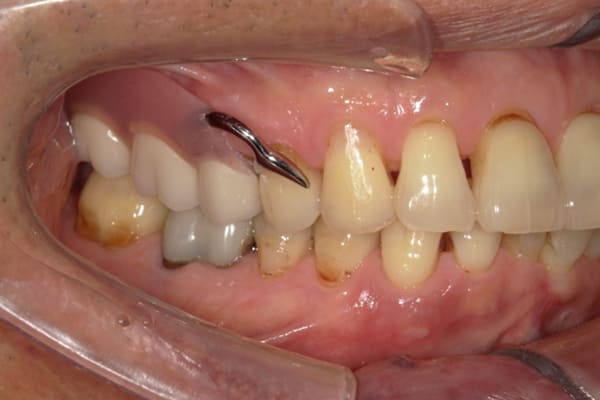

症例レポート[CASE.03]

入れ歯がガタつく、

見た目も改善したい

- 性別・年齢

- 女性(50代)

- 主訴

- 入れ歯がガタつく、何度調整してもよくならない。できれば見た目も良くしたい。

- 治療

-

- 上顎精密金属床部分入れ歯

- ジルコニアクラウン3歯

- 治療期間

- 約4か月間

- 費用

- 上顎精密金属床部分入れ歯:55万円

(ミリング、ラベット加工込み) - ジルコニアクラウン:11万円×3歯

合計:88万円(税込)

上あごに接する入れ歯に違和感がありになっていたとのことで、プラスチックが大きく削られた入れ歯をされていました。

そのため入れ歯の安定が悪く、お食事の際に入れ歯が動き、がたつきを感じられている状態でした。

前歯にバネにより見た目の問題も抱えておられました。

かみ合わせが低くなった歯を本来の高さに戻し、保険では使用できない歯に負担のかかりずらいバネで、歯の保存、審美性を確保しました。

前歯にバネを設定せず、見えない奥歯に維持力をもたせたバネを用い、またバネのかかる歯の負担軽減を目的に、被せ物は繋げることで強度を増す設計とすることで、入れ歯が動かずガタつき、審美性不良が解消されました。

部分入れ歯と対合歯

入れ歯を修理する中で、入れ歯の上あごの接触面積ではなく、厚みに対しての違和感と診断し、薄い金属を用いた従来の厚みを1/3程度にした入れ歯にすることにより違和感は消失しました。